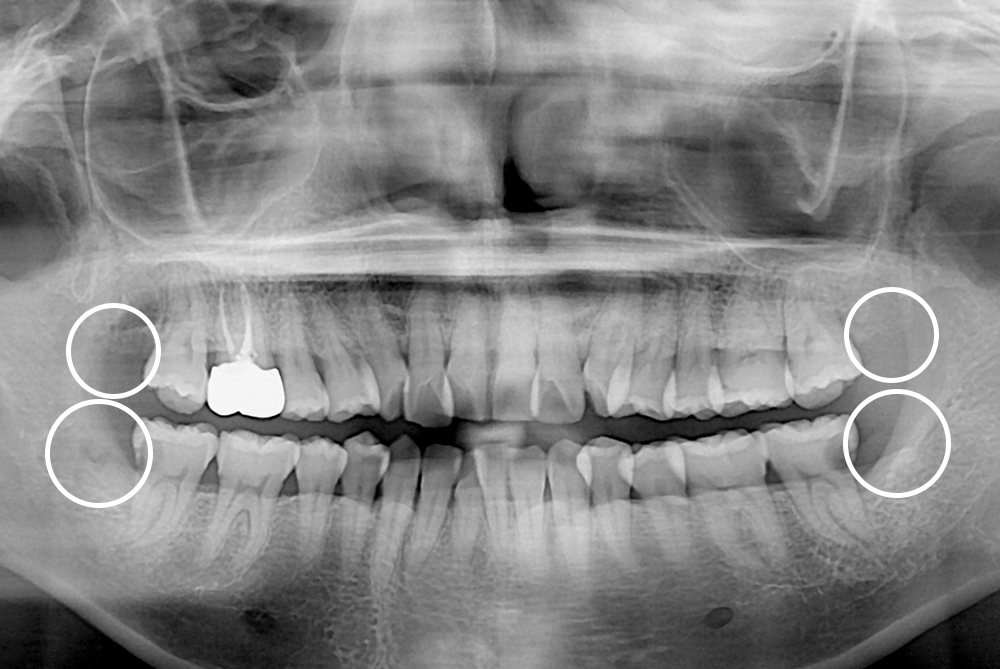

[사랑니] 매복 사랑니 발치

치료후 : 2019-07-31

세종치과는 구강악안면외과학 박사이신 원장님이 발치하는 치과입니다.